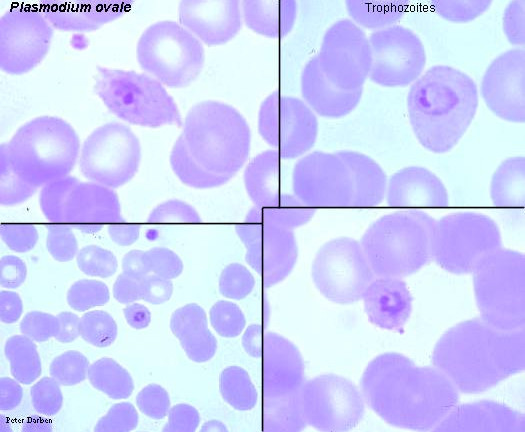

plasmodium ovale stadia schizogonii krwinkowej

plasmodium ovale stadia schizogonii krwinkowej